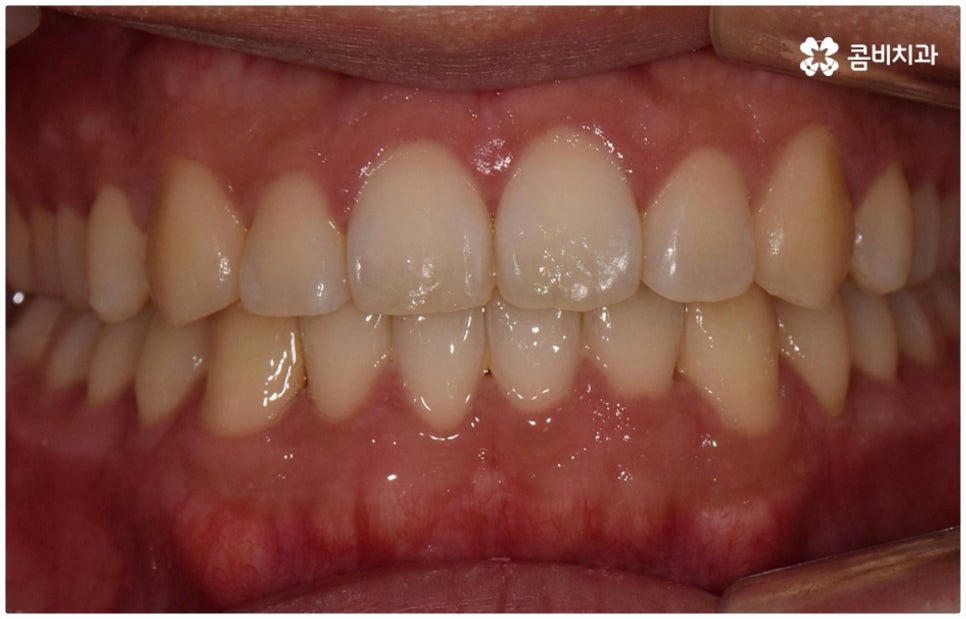

물론 교정 치료에 적기가 정해져 있는 것은 아니기 때문에 성인 이후 중장년 환자분들이라도 교정 치료가 불가능하지는 않으며 상황에 따라 비수술적인 방법으로도 얼마든지 불편함을 줄일 수 있는 경우가 있으니 정확하게 진단한 후 각자에게 맞는 교정 계획을 세워 무리하지 않게 치료를 진행하시길 바라고 있어요. 특히 턱관절과 관련된 부분을 개선하기 위해서는 양악 수술 밖에 방법이 없는 것이 아닌가 생각하셨던 분들이라면 먼저 치과에 내원하셔서 검진과 상담부터 진행해 보시면 마음의 부담을 덜 수 있어 좋을 거예요. 부정교합 3급 치열 (절단교합과 일부 반대교합이 병행되어 있음) 을 가지고 있는 성인분도 교정 치료를 통해 훨씬 자연스럽게 개선이 가능할 수 있으며, 관련 기술 개발 및 미니스크류 등 여러 장치의 발전을 통해 예전에는 적용이 어려웠던 케이스들도 이제는 교정 치료의 도움을 받을 수 있습니다.

위 사진은 이해를 돕기 위한 이미지이며, 환자의 동의하에 진행되었습니다.

전체 치료 기간은 약 18개월이 소요되었으며,

개인에 따라 출혈 및 부작용이 발생할 수 있고,

환자마다 치료 결과 및 기간이 상이할 수 있으므로,

정확한 치료 기간 및 치료 계획은

치과에서 상담을 받아보시길 권장 드립니다.